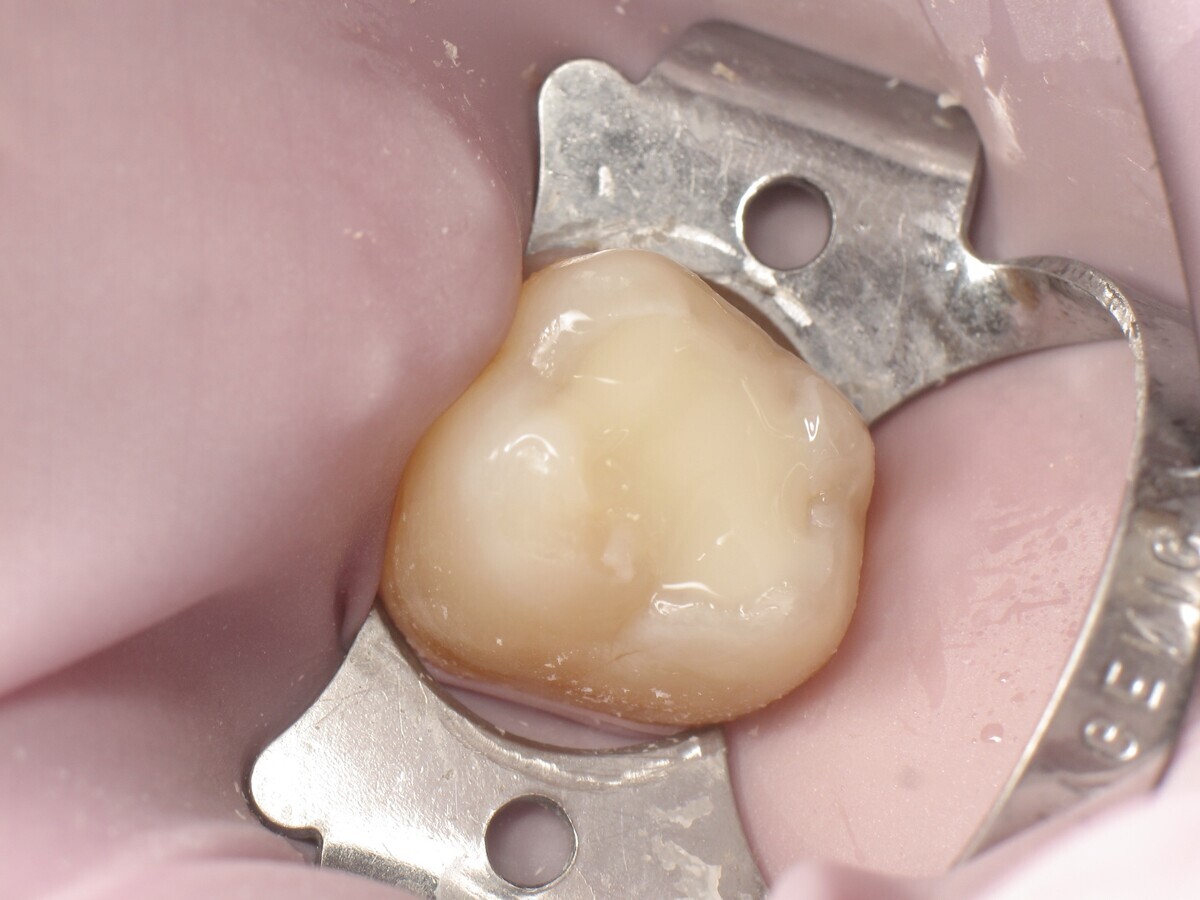

La secuencia fotográfica muestra la cavidad después de la aplicación y fotopolimerización del adhesivo y el modelado que se obtiene con el composite termoviscoso. Fotos: Yassine HARICHANE

Este artículo describe el tratamiento de una cavidad clase I en un molar utilizando un composite termoviscoso mediante la técnica de la almohadilla (Figura 1). En primer lugar, se registran los detalles anatómicos utilizando una resina transparente, fluida y fotopolimerizable (Clip Flow, VOCO). El diente se aísla con un dique antes de aplicar el composite transparente a la superficie oclusal con un cepillo aplicador y fotopolimerizar durante 10 segundos (Figuras 2-4). La almohadilla oclusal así obtenida (Figura 5) debe almacenarse en alcohol (etanol o isopropanol) para eliminar la capa de inhibición. Luego se limpia la cavidad clase I (Figuras 6 y 7). A continuación se graba el esmalte durante 30 segundos y la dentina durante 15 segundos (Conditioner 36, Dentsply Sirona) y luego se enjuaga bien (Figuras 8 a 10). Debido al bajo espesor de la dentina remanente, también se aplica protección pulpar (Telio Desensitizer, Ivoclar Vivadent) (Figura 11). Luego se frota el adhesivo sobre las superficies dentales durante 20 segundos (Futurabond DC, VOCO), luego se seca bajo una pulverización de aire sin aceite graso durante 5 segundos y luego se fotopolimeriza durante 10 segundos (Figuras 12, 13). Para una humectación óptima, el fondo de la cavidad se cubre con un compuesto fluido de baja viscosidad (GrandioSO Light Flow, A3.5, VOCO) y se fotopolimeriza durante 20 segundos (Figuras 14, 15). Utilizando el Dispensador VisCalor, un dispensador portátil que permite el calentamiento y la aplicación simultánea de resinas, la cavidad se llena luego con un composite termoviscoso bulk (VisCalor Bulk, A2, VOCO).

El composite calentado tiene una consistencia fluida para un perfecto manejo y se puede aplicar en capas de hasta 4 mm (Figura 16). A medida que se enfría hasta la temperatura corporal, la viscosidad del composite termoviscoso aumenta, lo que lo hace muy fácil de modelar (Figura 17). Finalmente, se realiza la fotopolimerización durante 20 segundos (potencia ≥ 1.000 mW/cm2, Figura 18). El uso de un composite bulk permite un llenado rápido en un solo paso. Si se requiere una segunda capa, la capa superior también se puede realizar con composite termoviscoso estético universal VisCalor en color A1 (VisCalor, VOCO, Figura 19), que se fotopolimeriza en incrementos de 2 mm. La consistencia innovadora del composite termoviscoso permite una reproducción fácil de la anatomía y una eliminación fácil del exceso de material (Figura 20) [Ilie et al. 2014]. A continuación se aplica la almohadilla oclusal creada previamente (Figura 21). La fotopolimerización se realiza primero con la almohadilla y luego sin durante 20 segundos cada una (Figuras 22 a 24). No se requiere material separador entre el material compuesto y la almohadilla. Debido a la eliminación previa de la capa de inhibición de la almohadilla, hay muy pocos o ningún punto de contacto, de modo que no se puede crear ningún enlace químico real entre la almohadilla y la resina. Los pocos puntos de contacto presentes solo significan que puede sentir una ligera resistencia cuando se retira la almohadilla después del primer ciclo de fotopolimerización.

Figura 17. Modelado de VisCalor Bulk.